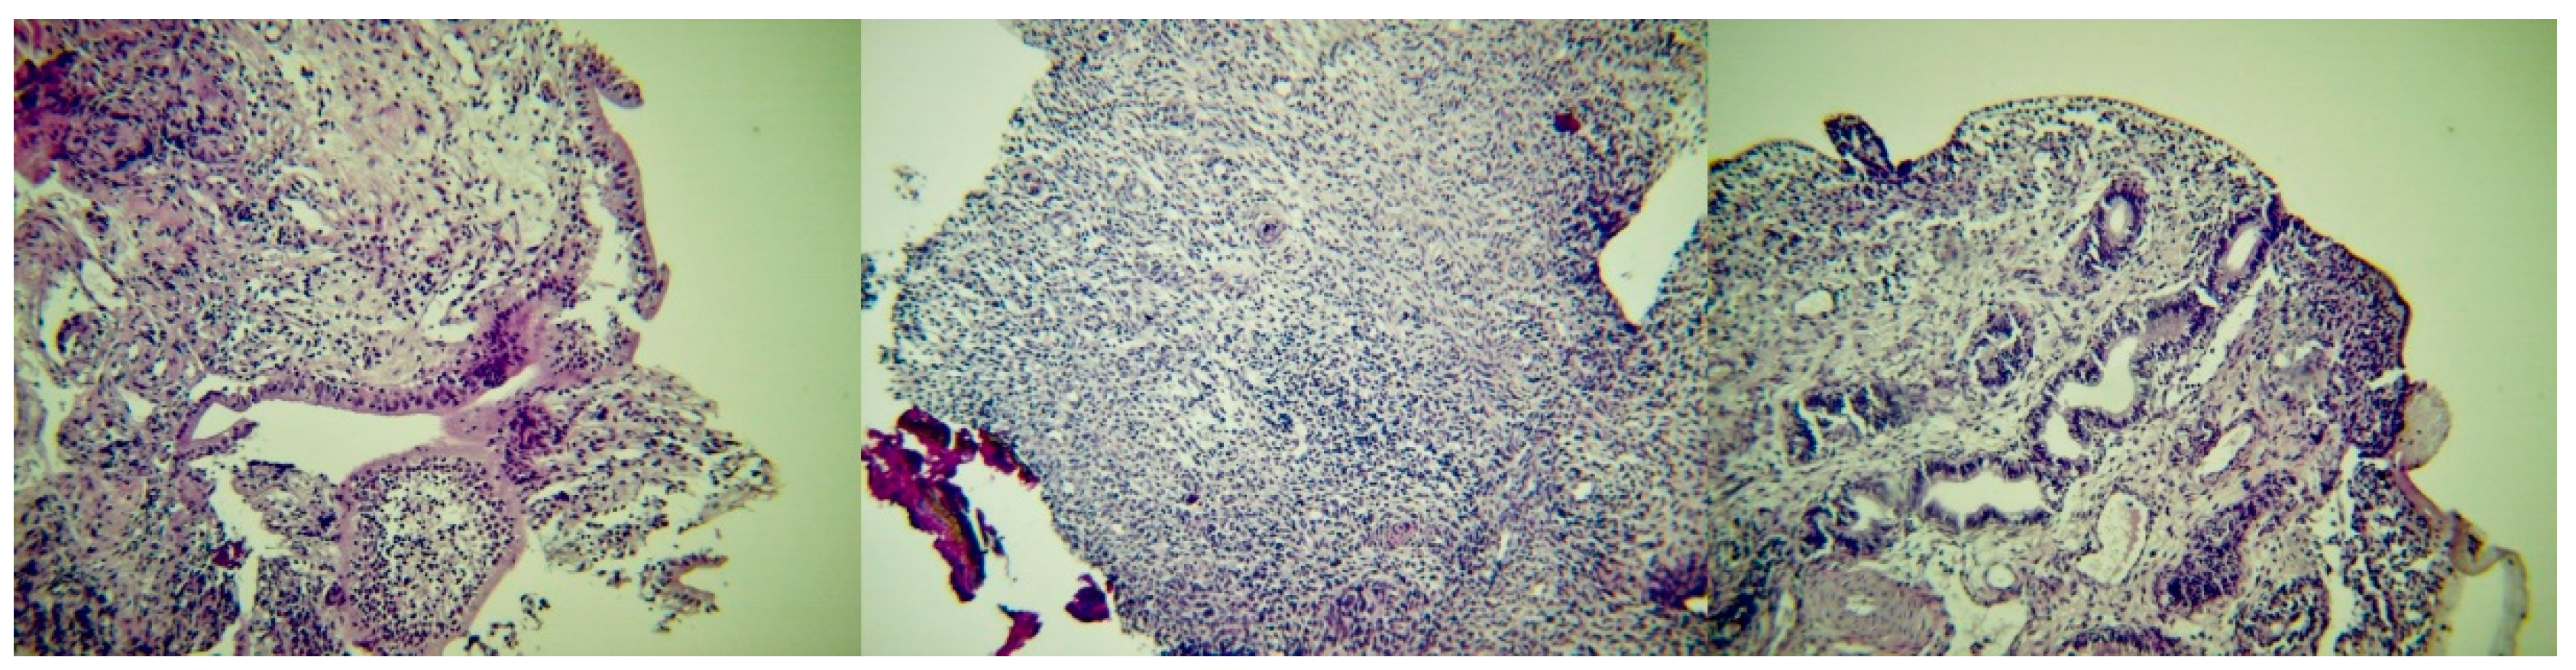

2.6. Histological Findings

In group I ewes (Figure 8), in samples collected on D7, the epithelium of the endometrium had a loose structure, with high cylindrical-like cells, which contained vacuoles. There was intense vascularisation with lymphocytic infiltration, which occurred mainly subepithelially and occasionally around the uterine glands. These could be easily observed. The myometrium appeared to have lost its fine structure; hyperaemia and extravasation were evident therein and it also had a loose appearance. On D14, the epithelium of the endometrium appeared destroyed with intense neutrophilic and lymphocytic infiltration; there was intense vascularisation and extravasation. There was intense presence of lymphocytes in the myometrium. On D24 and D27, the epithelium of the endometrium included cylindrical cells, with several small glands with small diameter being clustered in groups; the epithelium of the glands was cuboidal. There was intense presence of lymphocytes in the endometrium, whilst no inflammatory cells were observed in the myometrium, which included intense vascularisation and extravasation. On D34, in the sample from one ewe the epitheliium of the endometrium was characterised by single-layered cells, whilst in the sample from the second animal no epithelium could be observed. The uterine glands were collapsed and had fully regressed. The myometrium was thickened; no cellular infiltration could be observed therein in the sample from one ewes, whilst in the sample from the second animal there was evidence of intense cellular infiltration. On D42 and D44, there were single-layered cells on the epithelium of the endometrium, but this was not absolutely intact, as there were areas in the samples that no epithelium could be seen. Cellular infiltration in the myometrium was still evident. On D62, the border between the endometrium and the myometrium could not be distinguished; there were leucocytes and mild vascularisation therein.

In group C ewes, in samples collected on D7 and D14, the epithelium of the endometrium was intact, with cuboidal- to cylindrical-like cells; these contained vacuoles. There was clear hyperaemia with small-degree neutrophilic infiltration. The uterine glands were observed easily and had also cuboidal- to cylindrical-like epithelial cells. The myometrium included trophoblast-like cells and vacuoles. On D24 and D27, the epithelium was still intact, but height of epithelial cells was decreased. The uterine glands had a smaller size compared to previous samples. Progressively, the thickness of the myometrium reduced. On D34, the epithelium of the endometrium was characterised by single-layered cells. The uterine glands were collapsed and had fully regressed. Leucocytic infiltration was characterised by presence of lymphocytes. On D42 and D44, there were single-layered cells on the epithelium of the endometrium, still with lymphocytic infiltration. Finally, on D62, the border between the endometrium and the myometrium could not be distinguished and the entire uterine wall was observed as one entity.

Median score for total number of leucocytes in samples from I ewes was higher than in C ewes: 4 versus 3 (p = 0.014); differences between I and C ewes in median scores for neutrophils and lymphocytes, when these were considered separately, were not significant (p = 0.50 and 0.38, respectively). Lymphocytes always predominated in tissue samples, independently of sampling point or group.

Figure 8. Post-partum histological pictures of the uterus of ewes with experimentally induced uterine infection (group I), left to right: D7 (section of the endometrium, with cylindrical-like cells in the epithelium; occasionally, epithelium completely detached from the endometrium; presence of intense subepithelial infiltration primarily by lymphocytes with a few neutrophils as well), D27 (section of the endometrium, with intense infiltration by lymphocytes) and D42 (section of the endometrium, with cyboidal single-layered epithelium in almost the entire length of the endometrium; subepithelial infiltration primarily by lymphocytes; presence of vessels and uterine glands with cylindrical single-layered epithelium) (H & E, 200×).